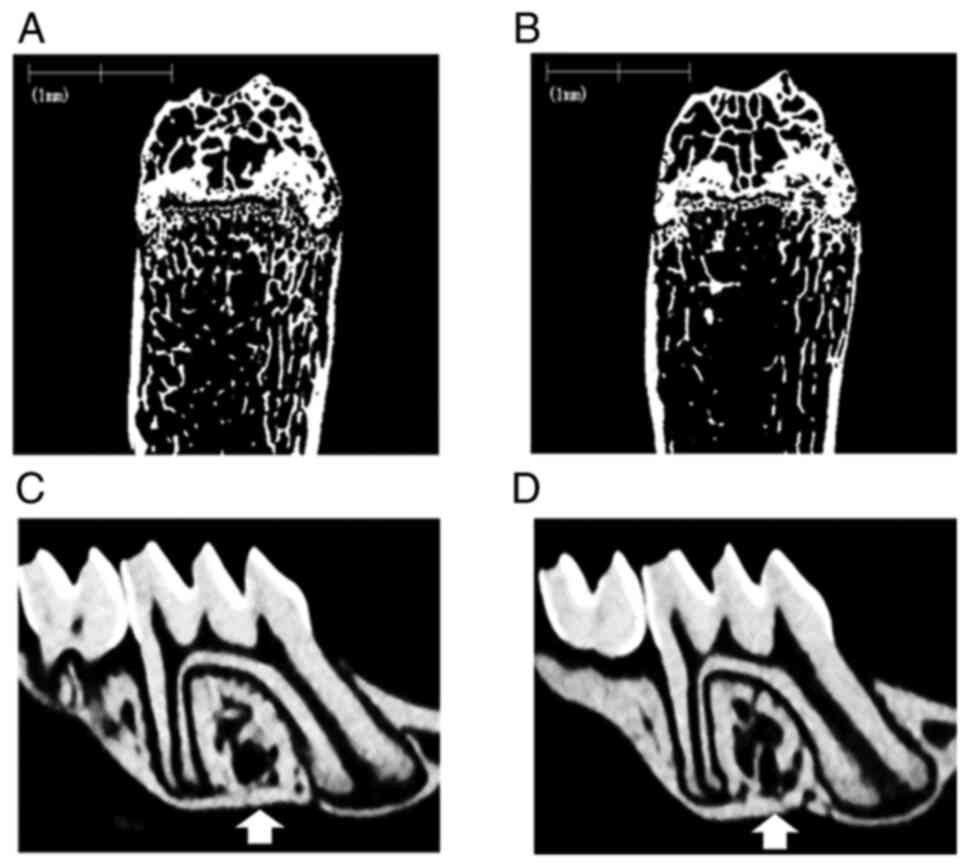

The most typical µ-CT images of the femur and maxillae for the G-CSF and control groups are shown in Fig. 2A-D. The G-CSF group exhibited a loss of trabecular bone in the femur (Fig. 2B) and the alveolar septum (Fig. 2D) compared with the control group (Fig 2A and C). Bone morphometric analysis of the proximal femurs and the alveolar septa of the first molar in the maxillae was performed to determine the BV/TV, Tb.Th, Tb.N, and Tb.Sp (Table II). Significant differences in the BV/TV, Tb.N and Tb.Sp of the proximal femurs were observed between the G-CSF and control groups. Significant differences in the BV/TV, Tb. N and Tb.Sp of the alveolar septa were observed between the G-CSF and control groups. G-CSF administration resulted in clear trabecular bone loss in not only the femur, but also the alveolar bone in the maxilla.

Figure 2

µCT examination of the femur and maxillae. The most typical µCT images of the femur for the (A) control group and (B) G-CSF group, and µCT images of the maxilla of the (C) control group and (D) G-CSF group, are shown. Trabecular bone loss in the distal femoral metaphysis and the alveolar septum of the first molar (white arrows) was observed in the G-CSF group compared with the control group. G-CSF, granulocyte colony-stimulating factor.